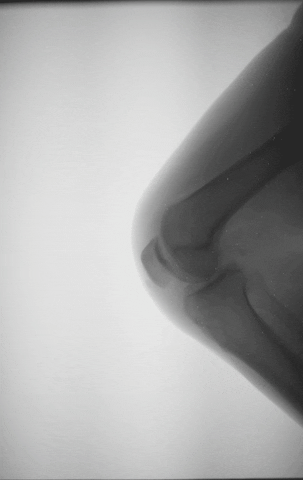

并且不止我一个人有脆弱的膝盖,数据显示:中国膝关节骨关节炎的患病率为8.1%,且女性的患病率约为男性的两倍!女性患病率为10.3%,而男性为5.7%。另外,女性骨关节炎发病时间比男性早10年,通常从40岁开始发病,男性则是50岁。

女性的骨盆更宽,骨盆和大腿之间的角度(也叫Q角)更大,所以膝盖在受力时,不是垂直状态,更容易向内塌陷,造成膝盖外翻。

因此,女性的膝关节磨损会更加严重,导致膝盖脆弱。

膝关节的周围,有肌肉和韧带在负责固定和支撑,当肌肉较为薄弱时,膝关节自己就不得不支撑起更多的重量。

和男性相比,很多女性的肌肉较为薄弱,所以平时膝关节的负担也相对重一些。

另外,还有研究显示,女性的膝关节软骨和男性相比,并不是等比例缩小,两者膝软骨体积和表面积有显著差异。

加强膝盖附近的肌肉,可以让肌肉帮助膝盖分担重量,从而减少磨损。尤其是臀腿部位的肌肉,比如大腿的外展肌、臀中肌等,都可以帮助稳固膝盖。

体重过高会给膝盖带来较大的负担,我们站起来或是走路时,膝盖的负重是体重的1~2倍;上下坡或上下楼梯时,膝盖的负重是体重的3~4倍;跑步时,膝盖的负重是体重的4倍;而蹲或跪,膝盖的负重到达了8倍!